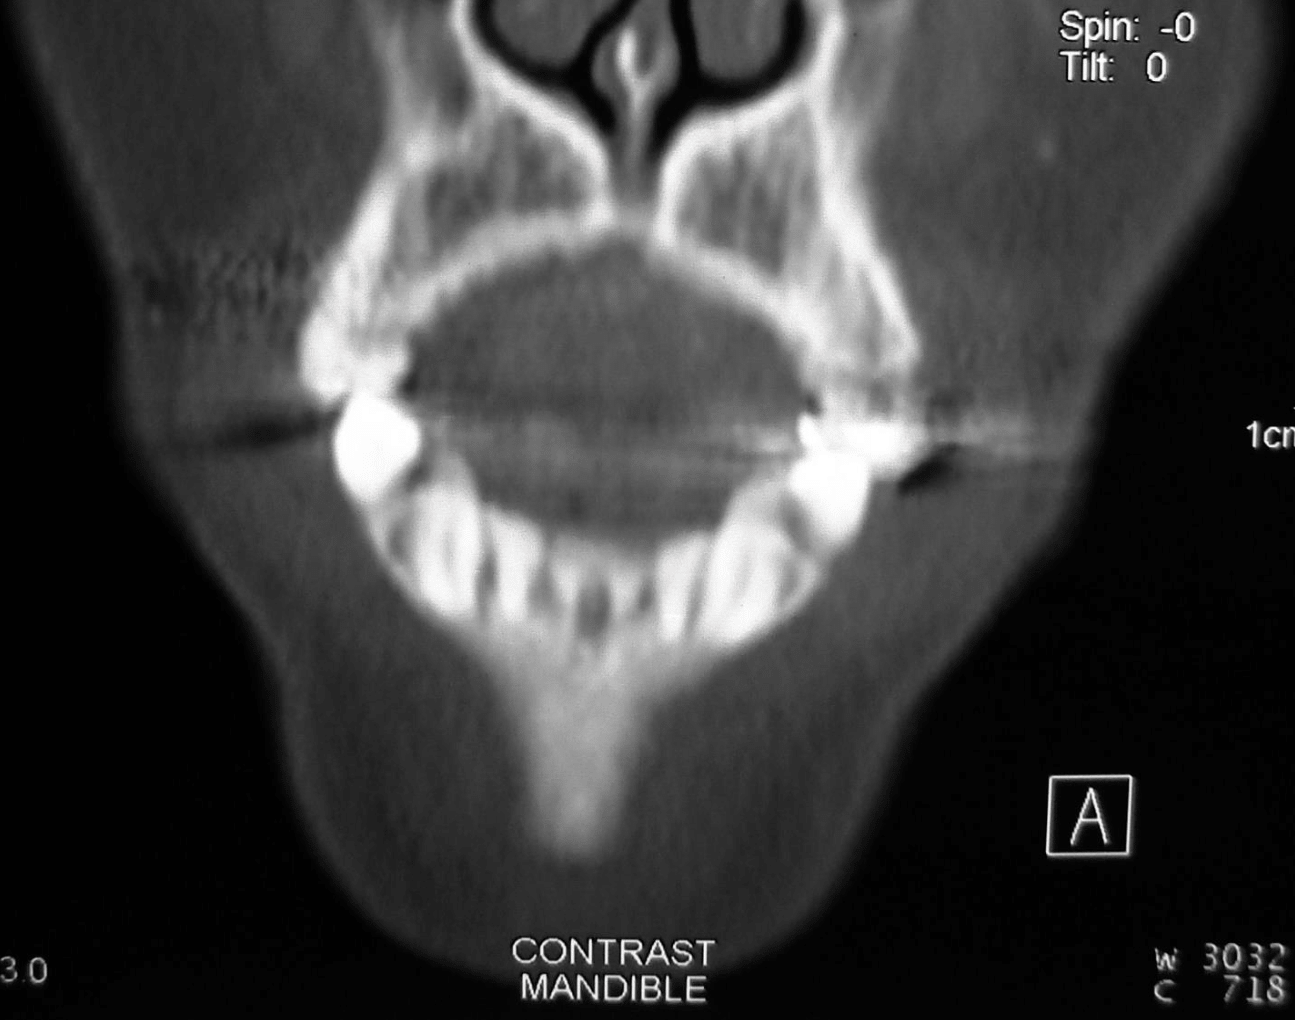

Preoperative radiographic examination including panoramic X-ray and C.T for evaluation of mandibular bone invasion by the lesion and evaluation of the neck lymph nodes (Figure 2A, B, C). Both the mandibular bone and neck lymph nodes were free. Whole body scan with Technetium-99m radiopharmaceuticals imaging was negative (Figure 2D). Clinical stage according to TNM system was T1N0M0.

Figure 2c CT coronal view for evaluation of bone invasion by GSCC.